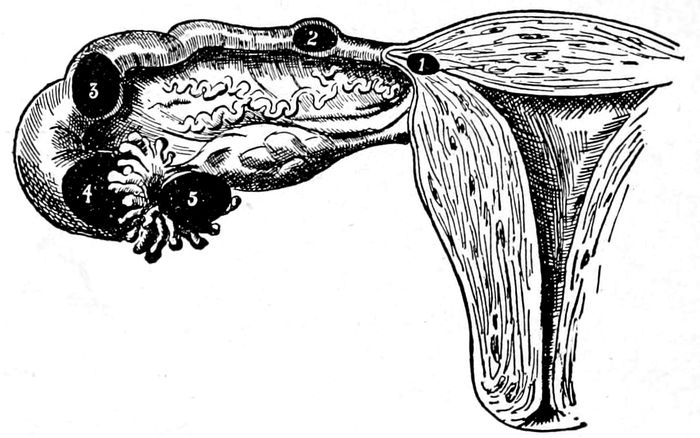

| 12. |

34 |